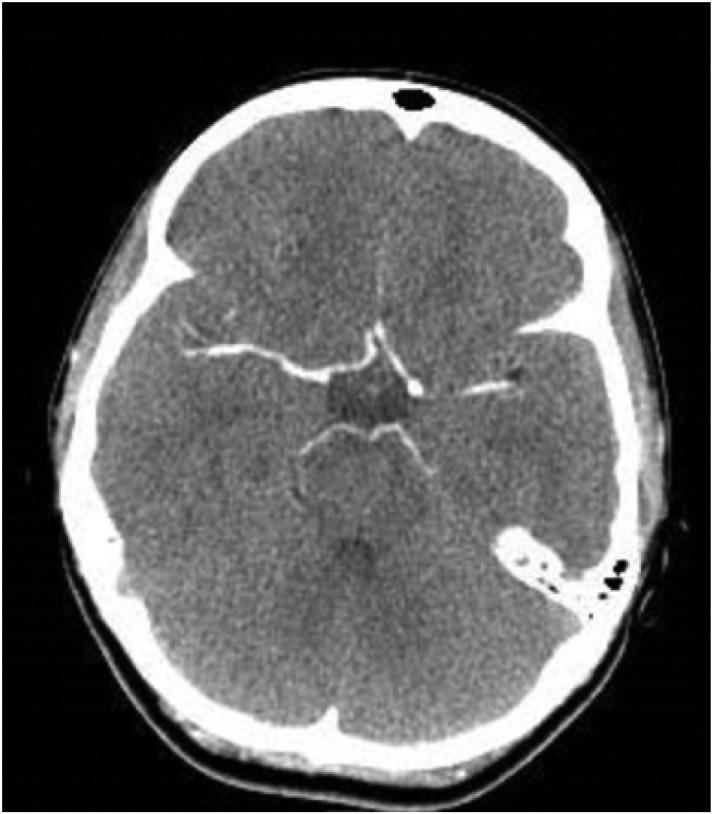

ThepatientunderwentanemergentCTofthehead (Image3)duetothechangeinmentalstatus.Theradiology impressionoftheCTrevealed “extensivevenousgas,which

Computedtomographyofthebrainofa77-year-oldman afterarapidchangeinmentalstatusshowingextensivevenous gas(whitearrows)intherightparieto-occipitalregion.

mayindicategasemboluswithpossibleevolvinginfarctionin therightparietalregion.Nohemorrhageorshift.Further evaluationwithmagneticresonanceimaging[MRI]maybe useful.Largegoiter.” Immediatelytheteamassessedthe patient’scentralvenouscatheterandfoundanuncappedline. Aftertheairwaswithdrawnfromtheline,thelinewas capped.Thepatientwastransferredtotheintensivecareunit atourhospitalforfurthermanagementandahyperbaric medicineconsultation.Heunderwentahyperbaricoxygen therapytreatmentwithresolutionofthegasontherepeatCT head.Afollow-upMRIrevealedmultifocalinfarctsin multiplevascularterritories.